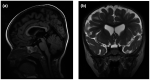

Methods and results: We present two unrelated cases of DYRK1A-Related Intellectual Disability Syndrome resulting from variants in DYRK1A. Both probands presented to the National Institutes of Health (NIH) with multiple dysmorphic facial features, primary microcephaly, absent or minimal speech, feeding difficulties, and cognitive impairment; features that have been previously reported in individuals with DYRK1A. During NIH evaluation, additional features of enlarged cerebral subarachnoid spaces, retinal vascular tortuosity, and bilateral anomalous large optic discs with increased cup-to-disc ratio were identified in the first proband and multiple ophthalmologic abnormalities and sensorineural hearing loss were identified in the second proband.